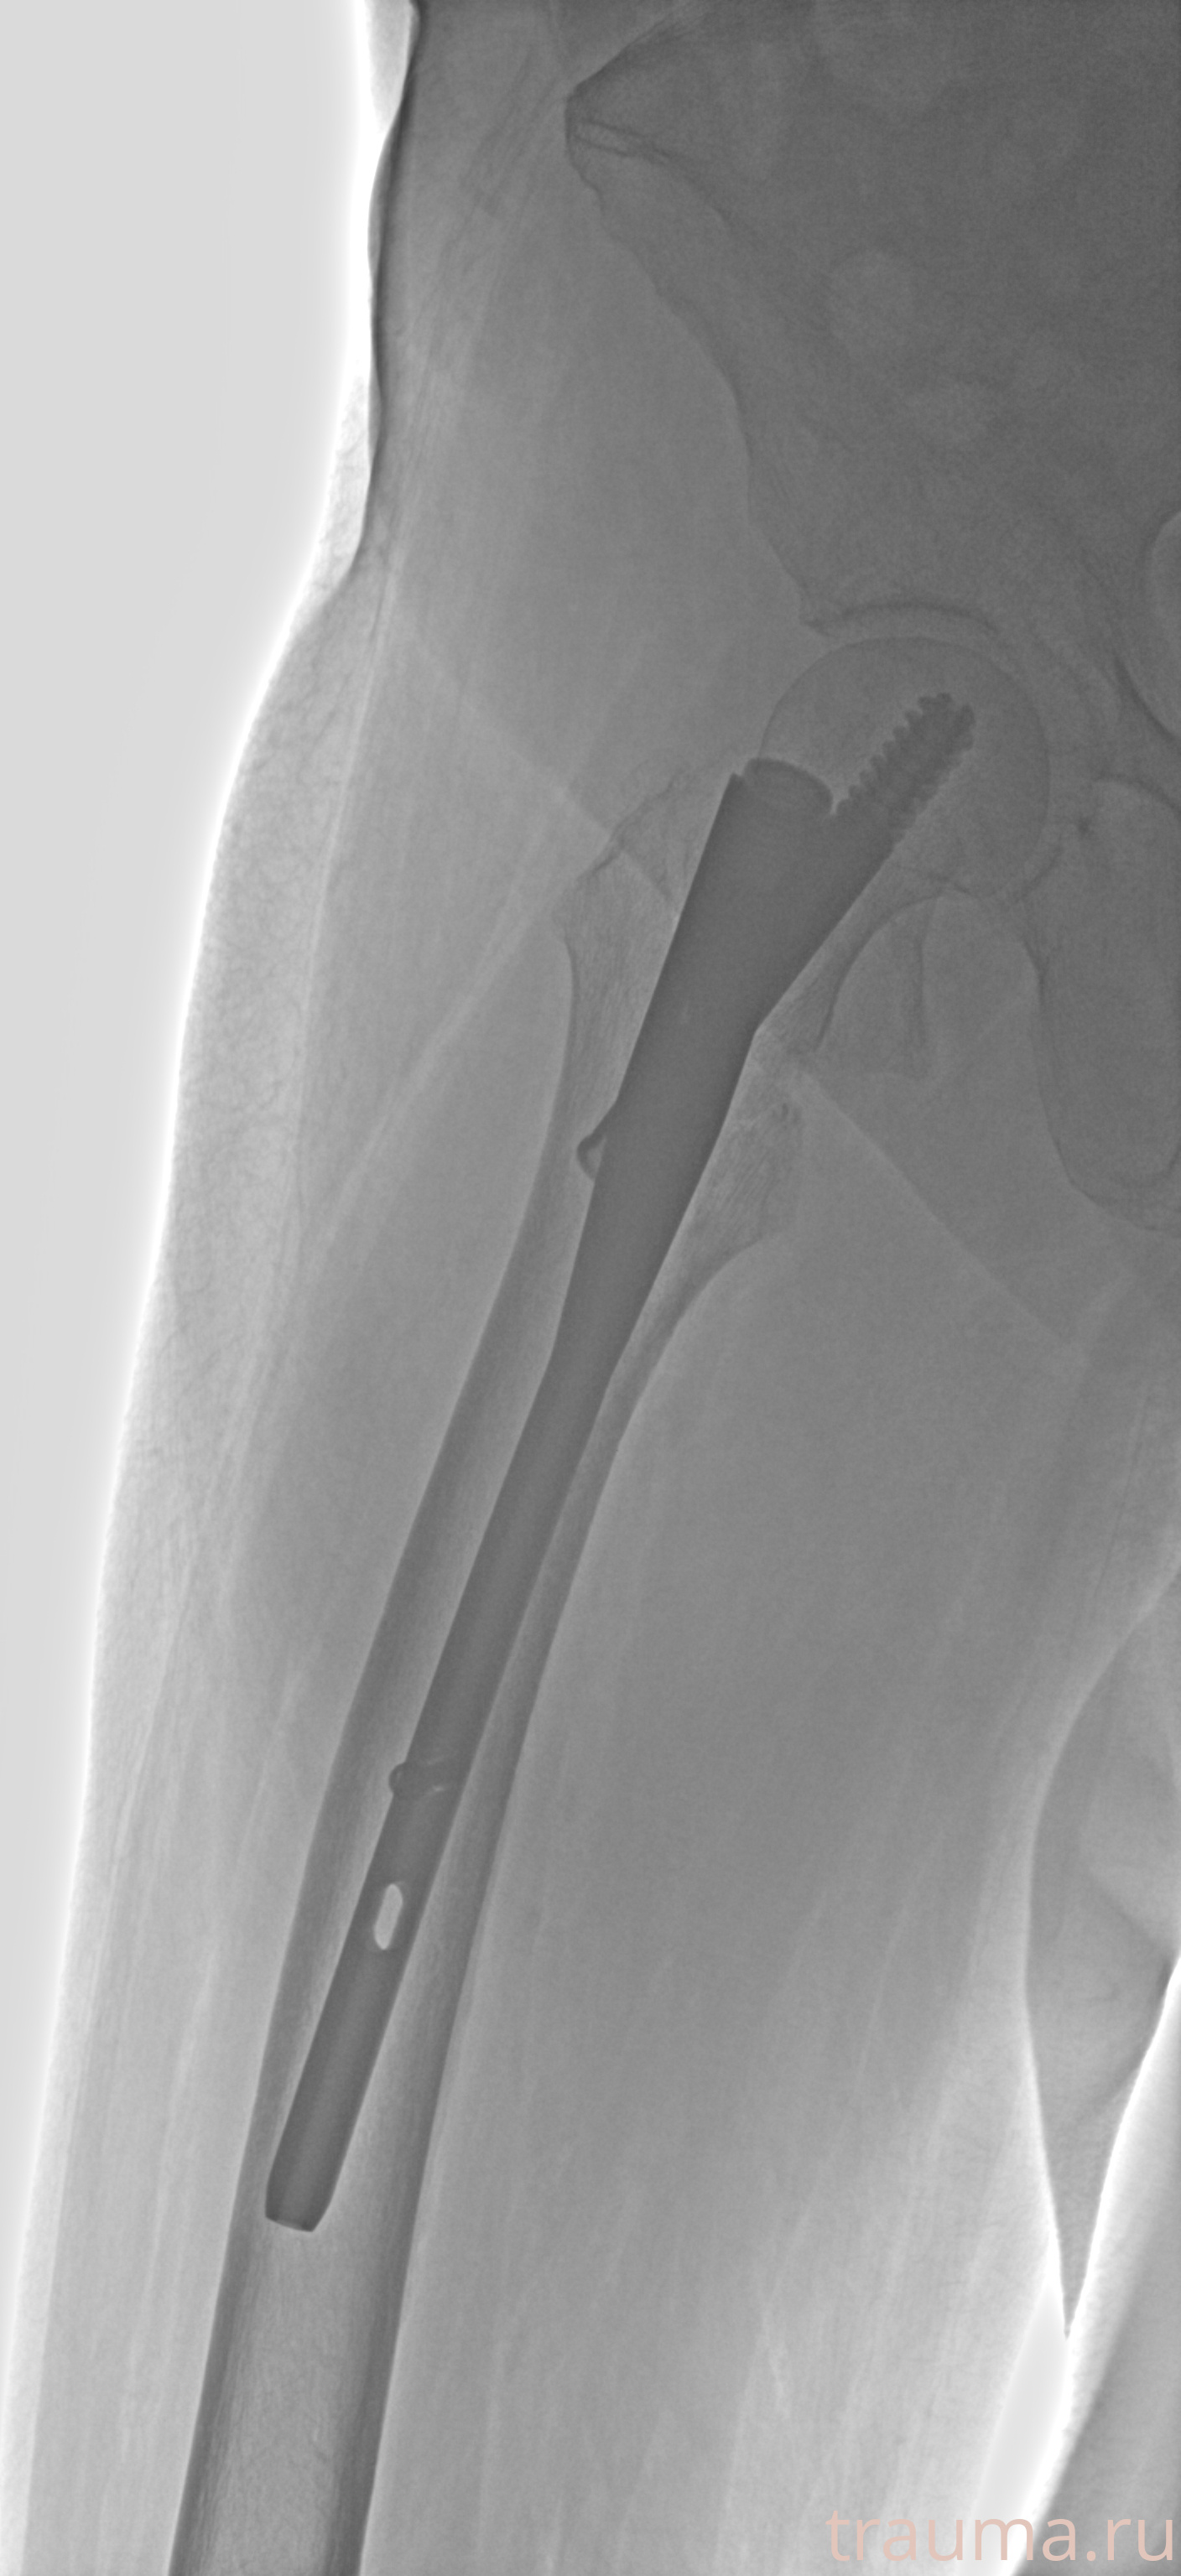

Рентгенограммы

Рентген на дому: по вашему адресу приезжает врач-рентгенолог, травматолог-ортопед с мобильным рентгеновским аппаратом, проводит диагностику травмы или заболевания, делает необходимые рентгенограммы, дает рекомендации по дальнейшему лечению. Получить качественные снимки в домашних условиях возможно благодаря уникальной методике, разработанной МосРентген Центром для института  Склифосовского